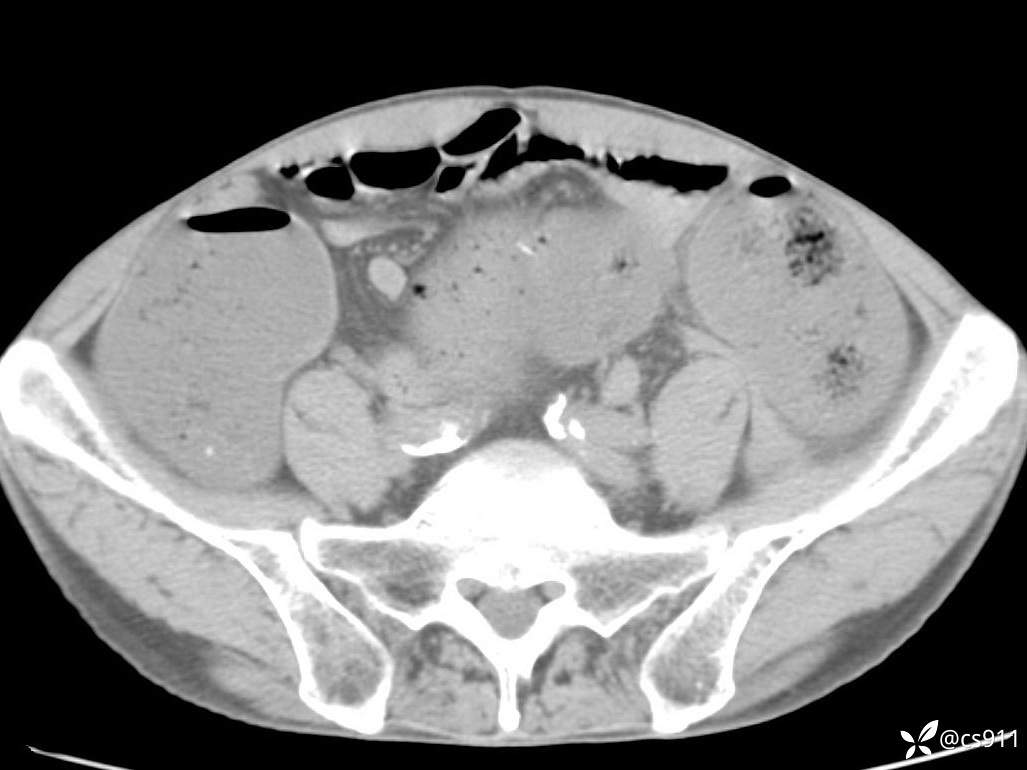

急腹症之急诊CT,原因?答案公布

男,77岁,腹痛、腹胀伴恶心呕吐1天。呕吐胃内容物,非喷射性呕吐,有咖啡色样胃内容物,诉有胃穿孔病史。查体:全腹平,下腹部压痛,全腹无反跳痛,叩诊呈浊音,移动性浊音阴性,肠鸣音减弱,1-2次/分。肛检:直肠未扪及明显肿物,可触及大量粪块。

T 36.6℃ P 80次/分 R 26次/分 BP 100/60mmHg

白细胞(WBC) H 14.55 10e9/L 4-10

中性粒细胞百分率(NEUT%) H 85.7 % 40-75

血淀粉酶(AMY) HH 1859 U/L 35-135

癌胚抗原(CEA) H 27.44 ng/ml 0-5

呕吐物 潜血试验 * 阳性 阴性

患者轮椅入室检查神志清楚, 能配合摆位和呼吸